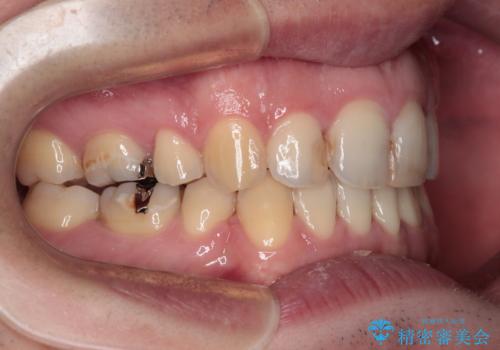

しゃくれて口が閉じられない ワイヤー装置での抜歯矯正

- 口がうまく閉じられないとのことで来院された患者様です。

上下唇をしっかり合わせようとすると、顎先が前方に突出してしまうほど口が閉じにくい状態でした。

口元の突出感を改善するために上下左右の第一小臼歯4本を抜歯し、ワイヤー装置にて矯正治療を行うこととしました。

また、上下前歯は舌の突出癖による開咬となっていたため、舌のトレーニングを徹底するよう指示しました。